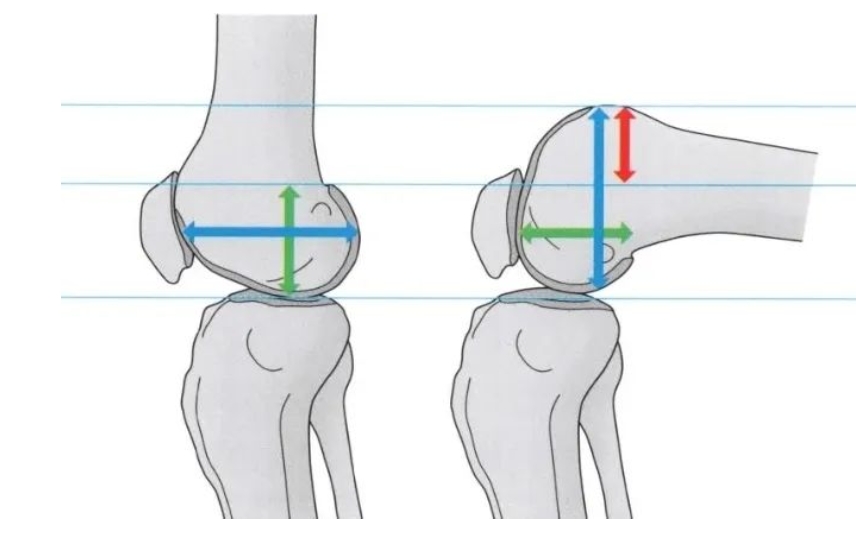

影响关节活动度的元凶之一